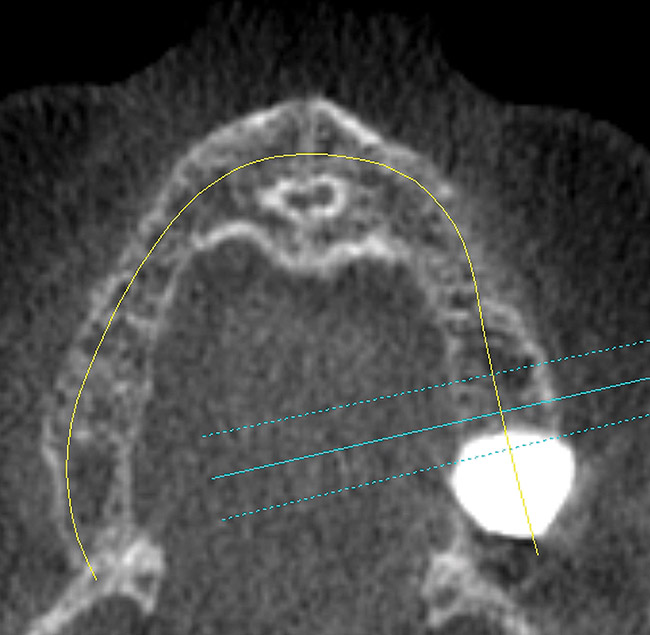

A 53-year-old woman in good health presented for the replacement of missing teeth on the maxillary arch and periodontal therapy of the mandibular arch. A CBCT scan was taken that revealed the need for bone grafting on the maxillary ridge and maxillary sinus areas in the panographic (Figure 14) and axial (Figure 15) views. Bone loss was noted on the facial plate areas of the anterior ridge. A treatment plan was created to graft the maxillary ridge and sinuses bilaterally, and then to place 12 dental implants to support a fixed prosthesis on the maxillary arch.The treatment plan for the mandible consisted of periodontal surgery to save her remaining teeth.

Figure 15  Axial view showing large facial defects.

Figure 15

Figure 18  Axial view 6 months post-graft showing substantial bone regeneration.

Figure 18